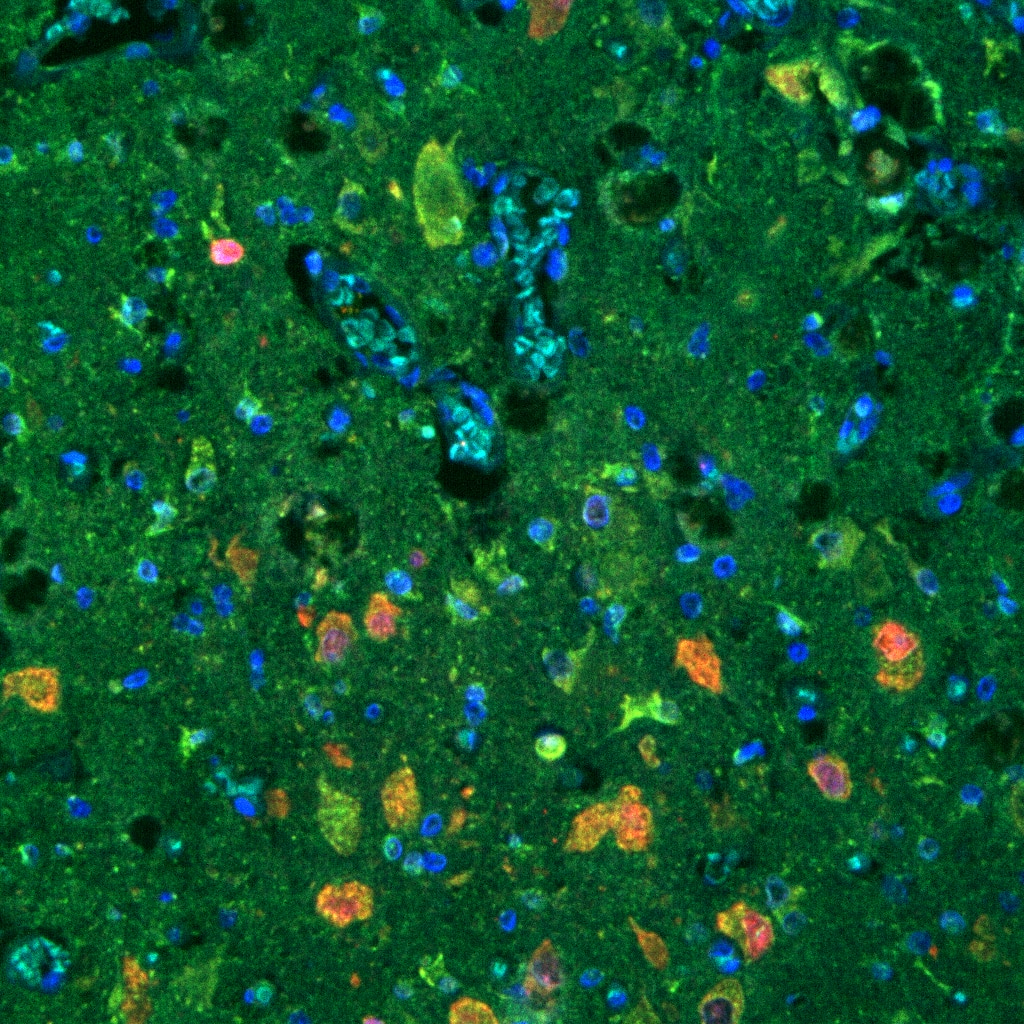

FH Reyes (Verified Customer) (09-24-2025) | pAKT (in green) worked very nicely inTSC mutated human brain tissue.